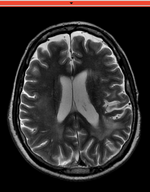

baseline & T2 before registration baseline to T2 after affine+nonrigid alignment DTI and T2 before & after registration